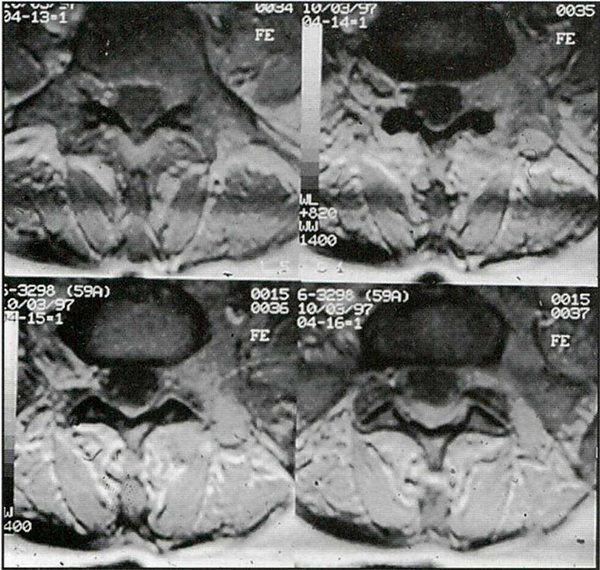

Caso 3: paciente de sexo femenino y 23 años de edad, con antecedentes de haber sido operada en su infancia de un tumor neurogénico abdominal, concurrió a la consulta con IRM que mostraban un tejido blando hiperintenso con respecto al LCR entre D12 y L4, ubicado en el espacio pre y paravertebral retroperitoneal, que se introducía dentro del canal espinal a través de los forámenes (Figs. 3 y 4). La paciente estaba asintomática. La oncóloga solicitó una biopsia para conocer la patología y luego poder indicar el tratamiento definitivo.

Fig. 3. IRM axial ponderarla en T1 que muestra un tejido blando hiperintenso con respecto al LCR ubicado a nivel extra e intraforaminal que invade el canal espinal.